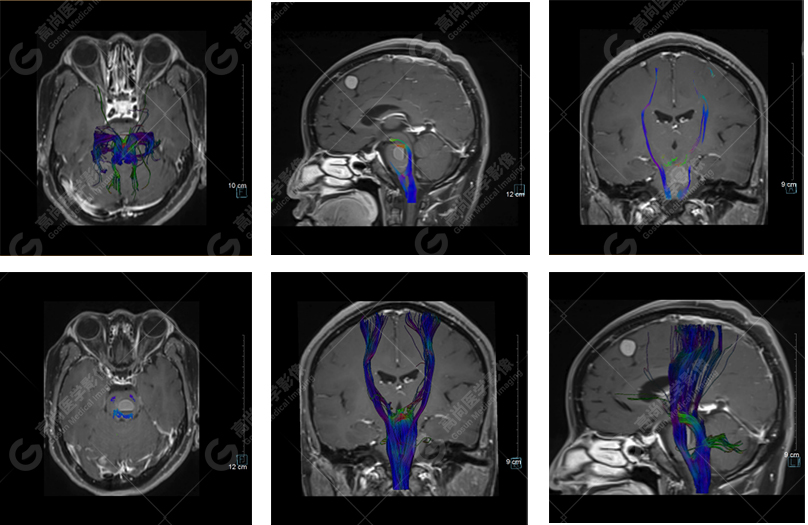

以上是常規(guī)顱腦MRI對(duì)病灶作出的診斷,可以看出,患者橋腦及大腦鐮各有一病灶,那么兩個(gè)病灶是否對(duì)顱腦神經(jīng)纖維束走行都有影像呢,下面是橋腦病變附近的神經(jīng)纖維束成像——皮質(zhì)脊髓束:

DTI成像示皮質(zhì)脊髓束橋腦段受壓向外側(cè)移位。圖像能清楚的顯示神經(jīng)纖維束與病灶的關(guān)系,是一種推壓移位的表現(xiàn)。